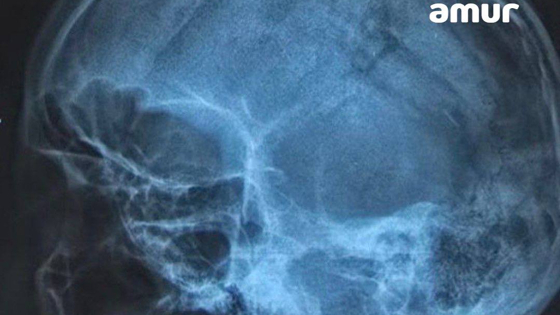

Некоторое время назад в больницу Владивостока доставили мужчину с острова Попова. У 50-летнего гражданина была разбита голова. Снимок показал, что череп проломлен в нескольких местах. Также выяснилось, что у пациента началось кровоизлияние в мозг. Сам он впал в шоковое состояние.

Врачи провели долгую и сложную операцию, в ходе которой смогли собрать череп буквально по кусочкам. Некоторые фрагменты пришлось убрать вовсе. Состояние пациента стабильное.